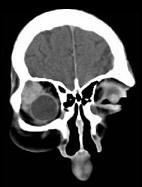

问题 男性,41岁,右侧眶外上方肿胀,可触及无痛性包块,CT及MRI检查如图所示,请选择最可能诊断()

选项 A.眶内血管瘤 B.眶内结核 C.眶内炎性假瘤 D.泪腺混合瘤 E.眶内囊肿

答案 D